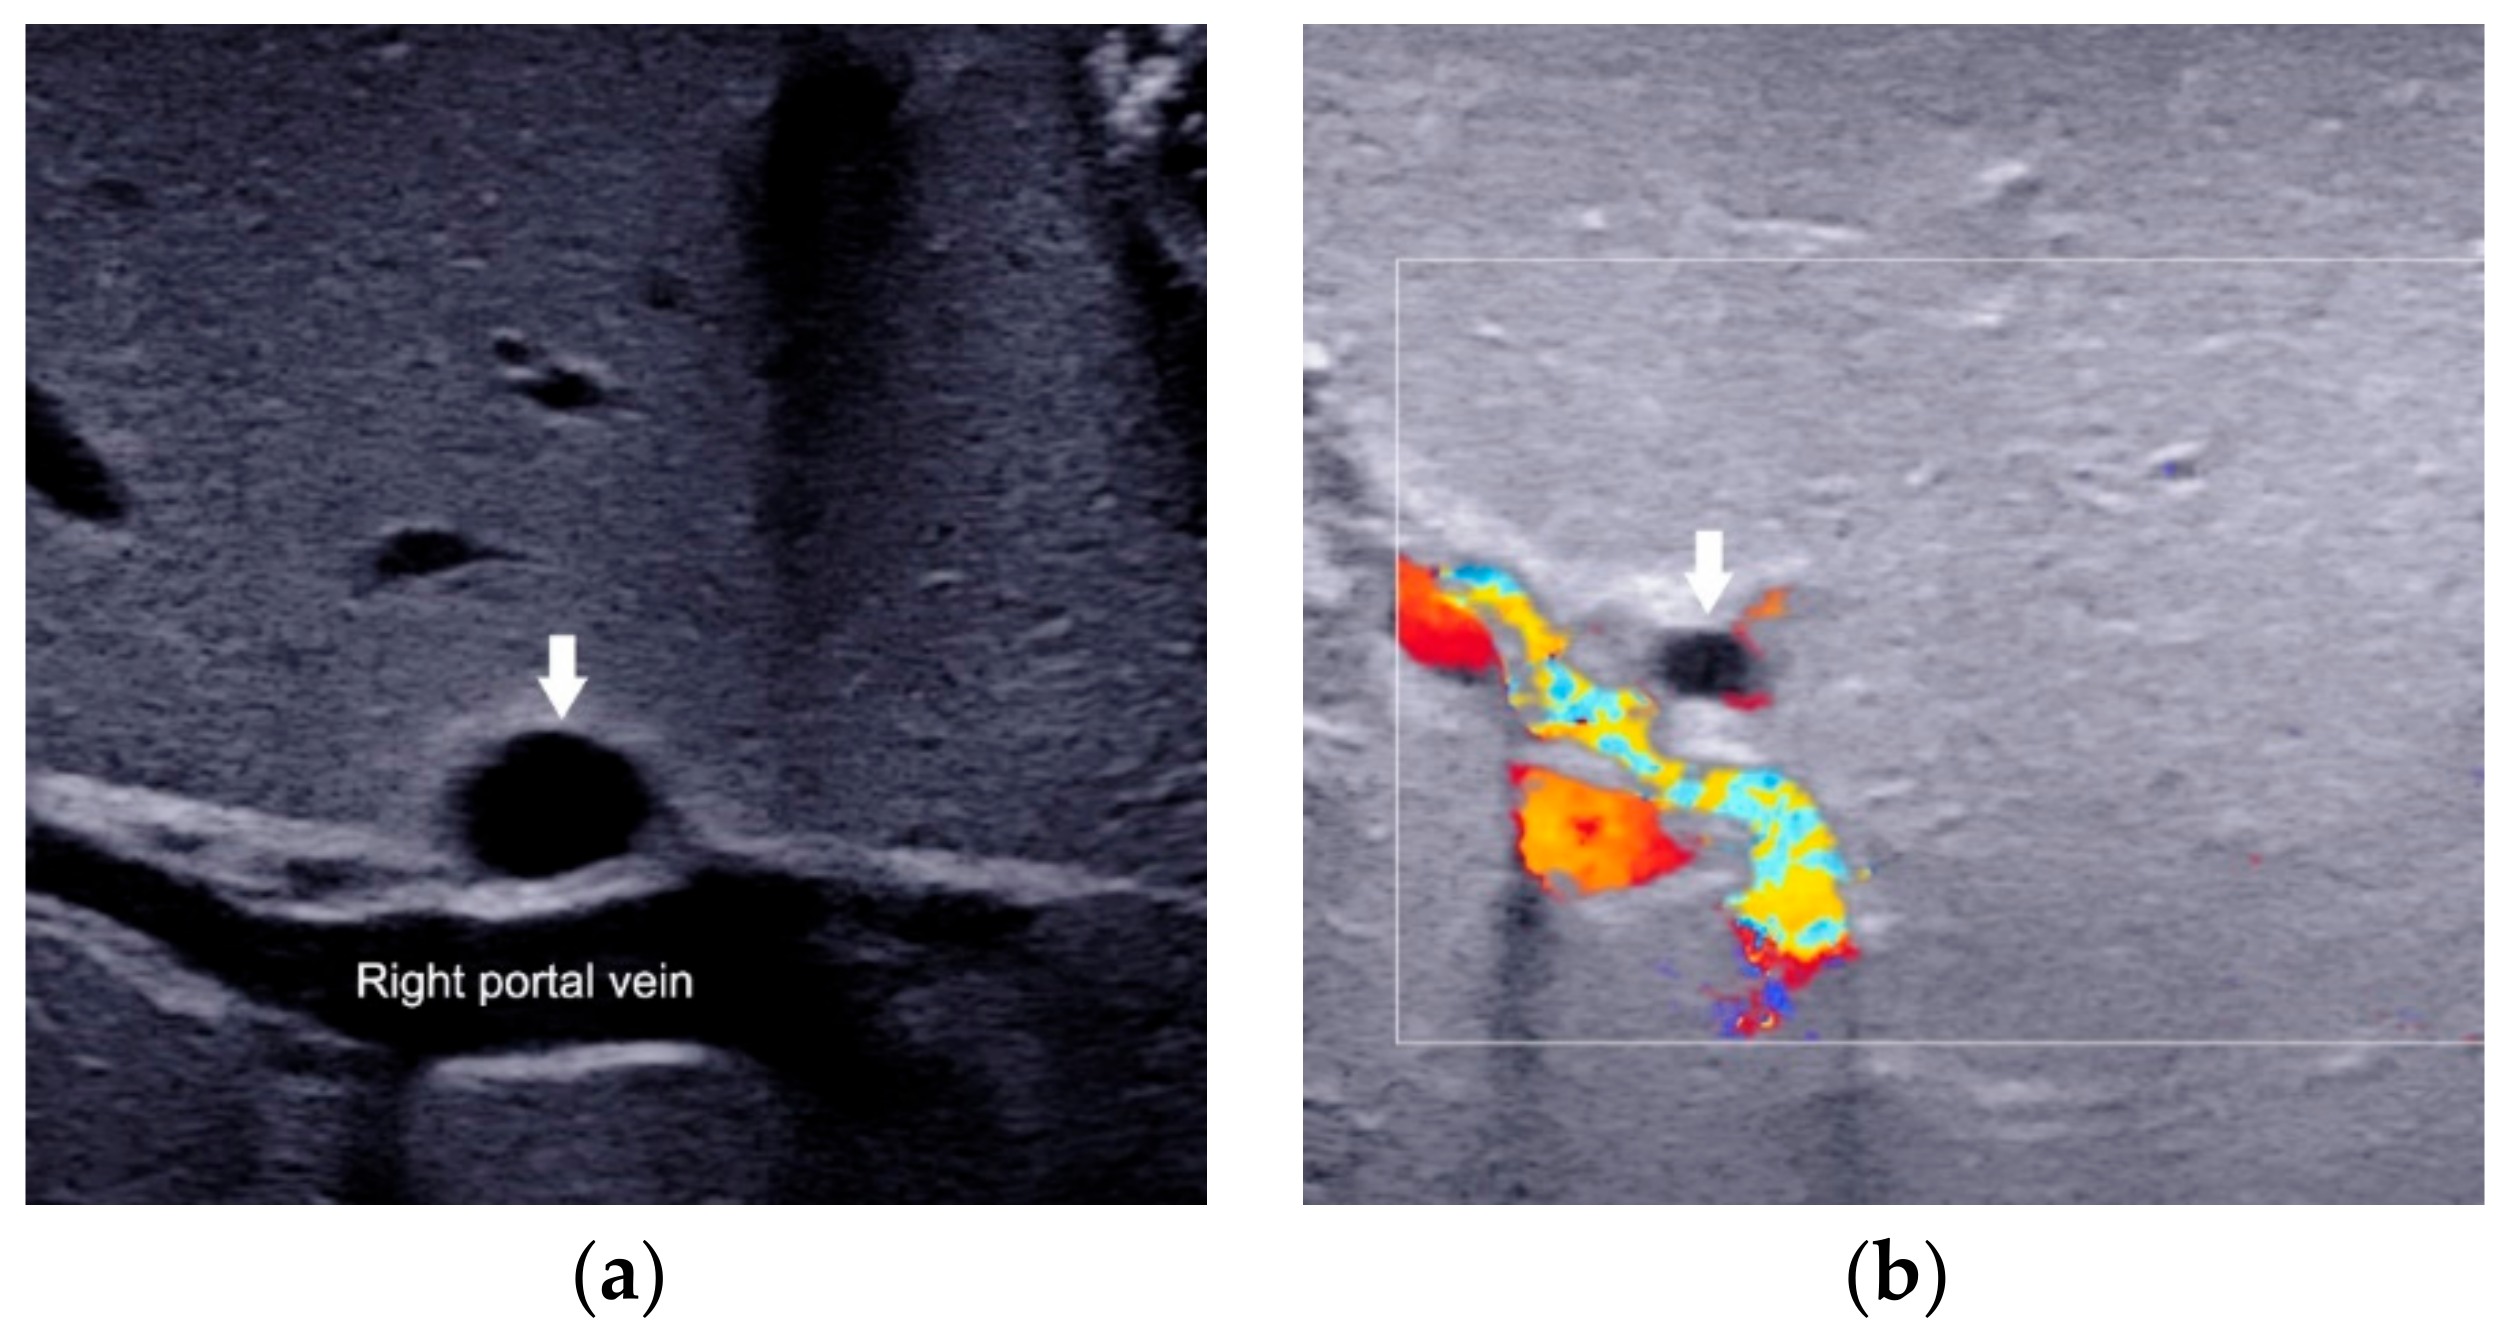

2.5. Other Helpful US Features

- Kim, W.S.; Cheon, J.-E.; Youn, B.J.; Yoo, S.-Y.; Kim, W.Y.; Kim, I.-O.; Yeon, K.M.; Seo, J.K.; Park, K.-W. Hepatic Arterial Diameter Measured with US: Adjunct for US Diagnosis of Biliary Atresia. Radiology 2007, 245, 549–555. [Google Scholar] [CrossRef]

- El-Guindi, M.A.-S.; Sira, M.M.; Konsowa, H.A.-S.; El-Abd, O.L.; Salem, T.A.-H. Value of hepatic subcapsular flow by color Doppler ultrasonography in the diagnosis of biliary atresia. J. Gastroenterol. Hepatol. 2013, 28, 867–872. [Google Scholar] [CrossRef]

- Lee, M.S.; Kim, M.-J.; Lee, M.-J.; Yoon, C.S.; Han, S.J.; Oh, J.-T.; Park, Y.N. Biliary Atresia: Color Doppler US Findings in Neonates and Infants. Radiology 2009, 252, 282–289. [Google Scholar] [CrossRef]

| HA diameter | Measured at the level of right proximal HA running parallel to the right portal vein. | 2.1 mm to 2.5 mm | 1.5 mm to 1.9 mm | Not recommended for diagnosis alone |

| Hepatic subcapsular flow | Vascular structures continued to the liver capsular surface on color Doppler US images. | Presence | Absence | Not recommended for diagnosis alone |